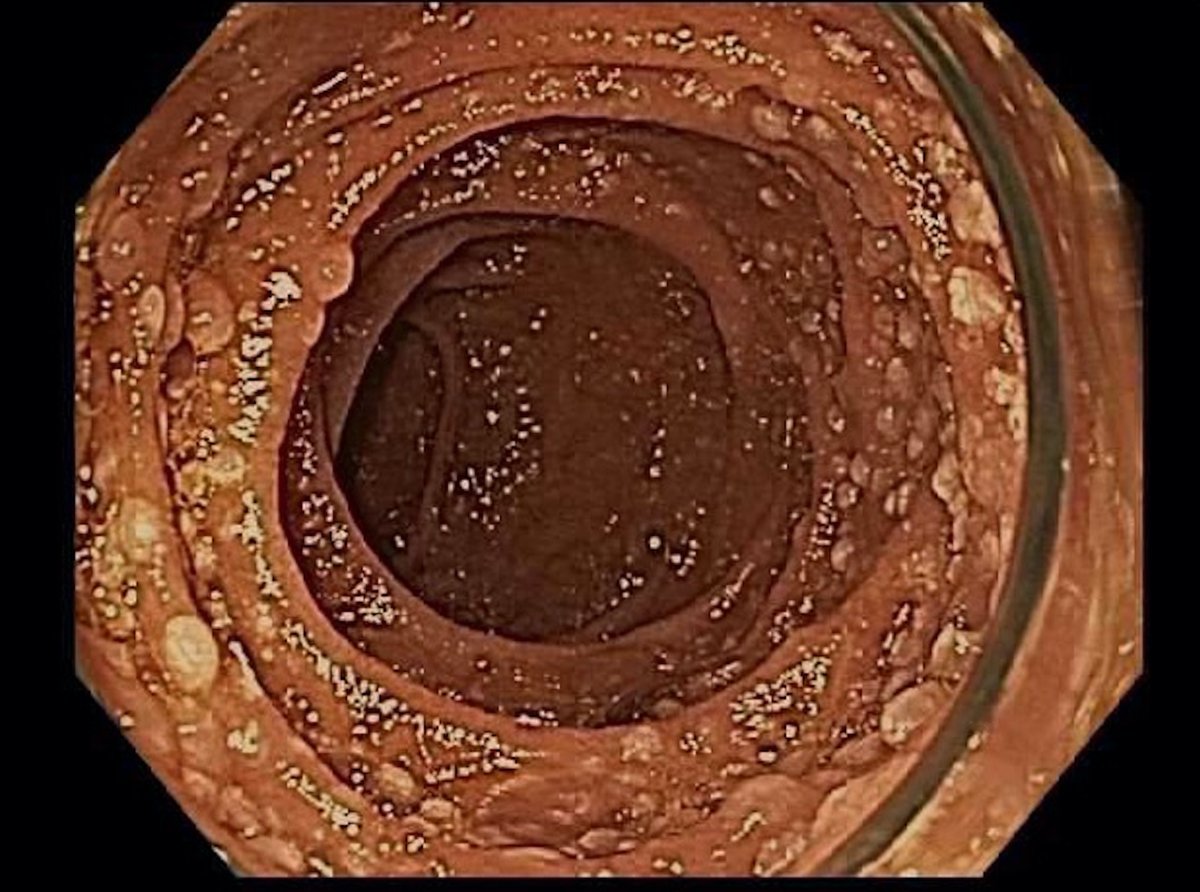

EGD: Diffuse nodular mucosa in the second portion of the duodenum

Thoughts? Differentials?

-Multiple small polyps; Often as an incidental finding on endoscopy performed for other reasons